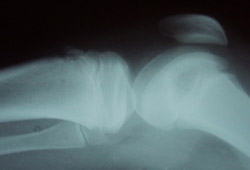

Later in the course of the disease, findings may include an enlarged tibial tubercle, irregular ossification of the tubercle, fragmentation of the tubercle, or formation of a separate ossicle.[1][5][Figure caption and citation for the preceding image starts]: Knee x-ray in a patient with OSD (lateral view)From the collection of Dr J. Rosen [Citation ends].

may be normal; often demonstrate enlarged tibial tubercle, sometimes with fragmentation of the apophysis